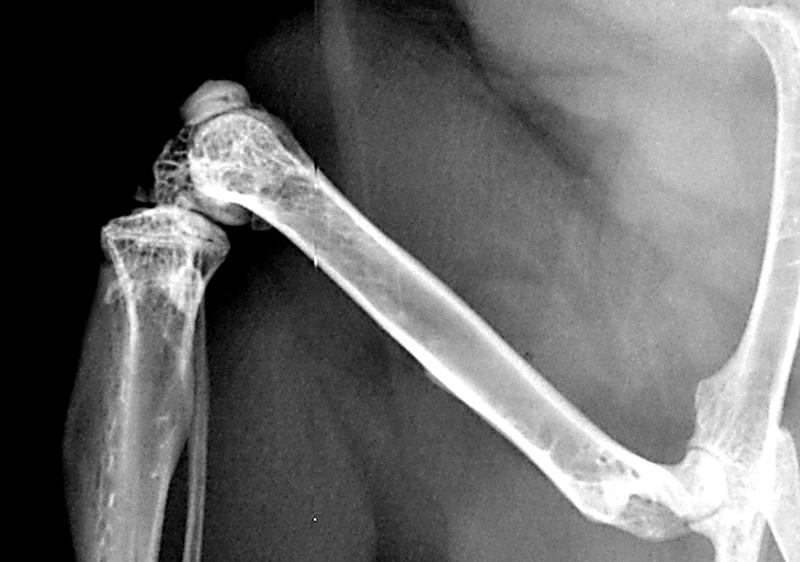

Oberschenkelknochen einer Maus

(c) Melanie Haffner-Luntzer / Uniklinikum Ulm